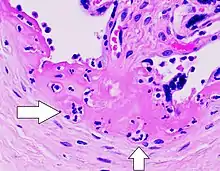

| Gross pathology of severe intervillositis, with dark red and soggy tissue. | |